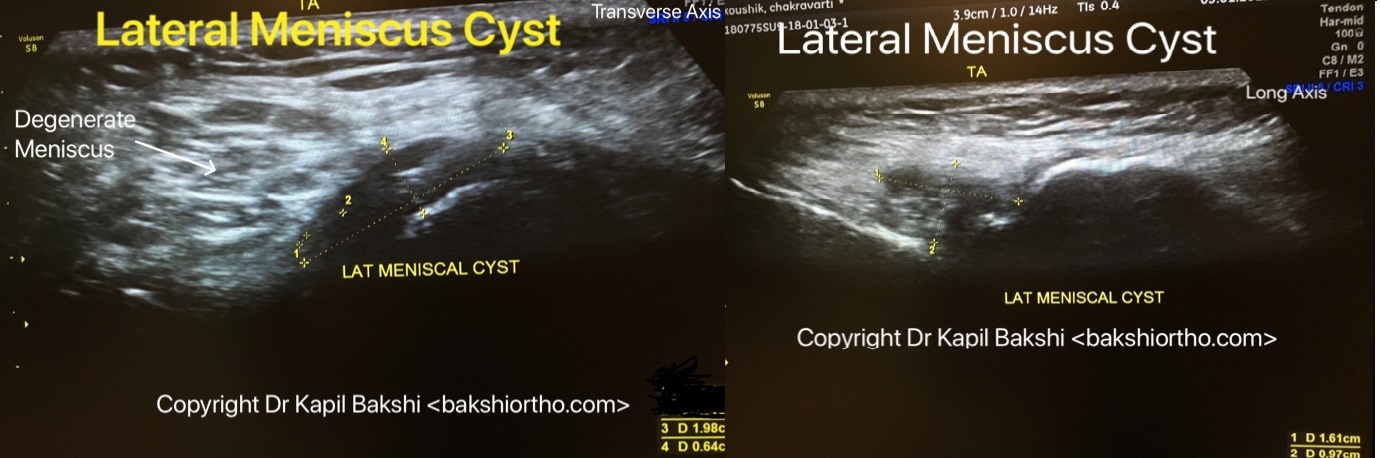

Dr. Kapil Bakshi (Bakshi Orthopaedics – A Patient Education & Guidance Resource)

Orthopaedic Surgery: Sports Medicine: Prolotherapy: Trauma: Rehabilitation: Arthroscopy: Spine: MSK Ultrasound